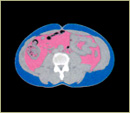

◎ MR検査

MRI(断層撮影)・MRA(血管撮影)を使って、脳を総合的に診断します。

頭痛、 めまい、 嘔吐、 手足のしびれ・ふるえ、 耳鳴り、 言語障害 歩行障害、 意識障害、 高血圧、 高脂血症、 糖尿病、 飲酒過多、脳卒中(脳出血、クモ膜下出血、脳血栓、脳塞栓等)は突然、前触れもなく起こりますが、その原因はひそかに進行しており、発症を前もって予測することは今まで困難でした。従来の方法では難しかった原因診断も、MRIの高性能化により、無侵襲の検査法が確率し、正確な画像診断が可能になりました。 症状がなくても脳動脈瘤、脳梗塞や脳腫瘍が見つかることがあります。脳動脈瘤の破裂の場合、最悪は死亡もあり得ますが、適切な検査と治療により発症の予防が可能です。また、万一発症した場合でも症状を最小限におさえることができます。